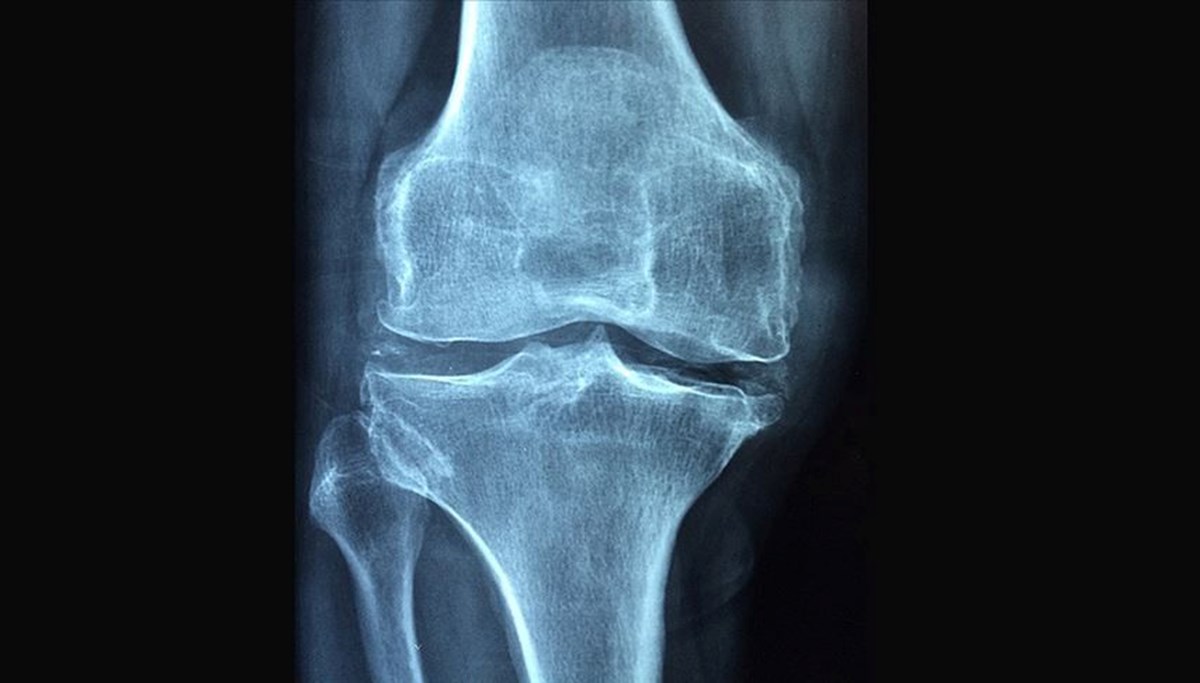

Polonyalı bilim insanlarının geliştirdği devrimsel bir ilaç, kırık kemiklere enjekte edilerek içeride sertleşiyor, plak veya vida kullanımına gerek kalmadan iyileşmeyi sağlıyor.

Polonyalı bilim insanları, ameliyata alternatif olabilecek ve kırık kemiklere enjekte edilerek tedavi sağlayan yenilikçi bir biyomalzeme geliştirdi. TVP World’ün cumartesi günkü haberine göre, söz konusu çalışma ameliyatlarda kullanılan plak ve vidalara gerek bırakmıyor.

VÜCUT İÇİNDE SERTLEŞEREK KIRIĞI SABİTLİYOR Szczecin kentindeki Batı Pomeranya Teknoloji Üniversitesi’nde iki yıllık araştırmayla geliştirilen polimer, vücut içinde sertleşerek kırığı sabitliyor. Üniversiteden Profesör Miroslawa El Fray, bu yöntemin hem tedavi sürecini hızlandırabileceğini hem de maliyetleri düşürebileceğini söyledi.

TEK SEFER UYGULANACAK Polimerin biyobozunur özellik taşıdığını belirten El Fray, “Kırık bölgesine tek seferde uygulanacak, sonrasında çıkarılmasına gerek olmayacak. Kemiğin iyileşme sürecini tetikleyecek ve ardından vücutta tamamen yok olacak” ifadelerini kullandı. Araştırmacılar, teknolojinin özellikle kış aylarında Polonya’da sıkça görülen bilek kırıklarında faydalı olmasını bekliyor. Biyomalzeme henüz patentlenmedi ve ticarileştirilmedi.